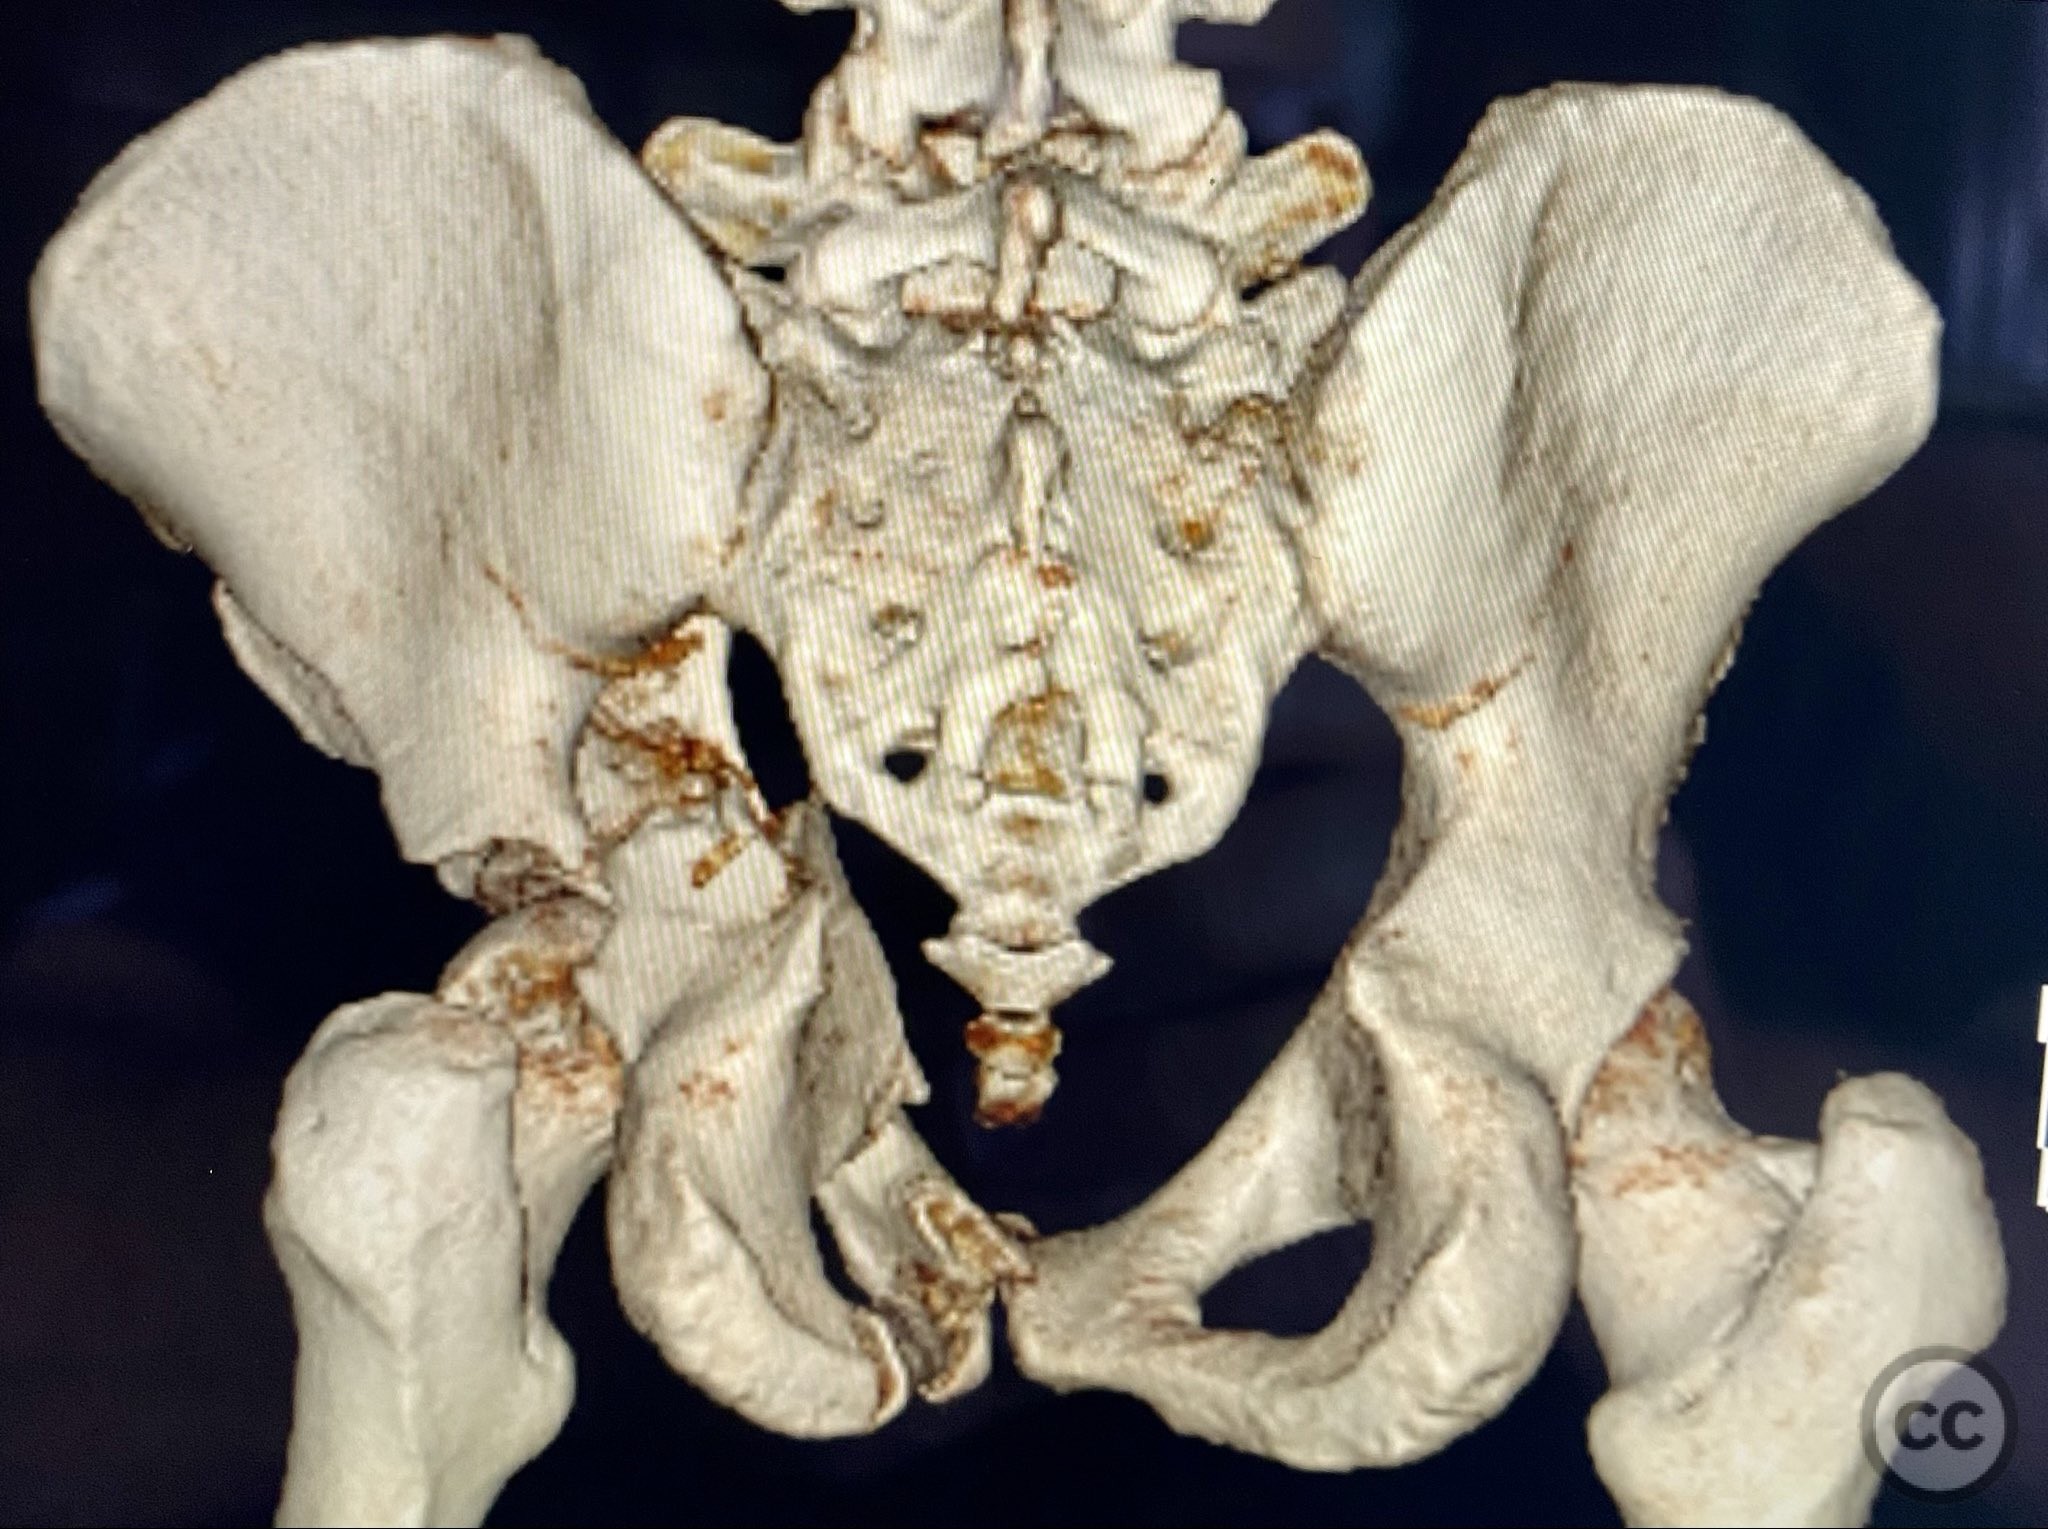

Clinical and radiological findings:  A patient presented with a displaced associated both column acetabular fracture, characterized radiographically by the presence of the "spur sign" on the anteroposterior (AP) pelvis film, indicating the caudal aspect of the intact ilium exposed by medial displacement of the articular fragments. The spur was more clearly visualized on the obturator oblique rendered image. Axial computed tomography (CT) images demonstrated the intact ilium, medially displaced anterior column (AC) and posterior column (PC) fragments, and provided detailed visualization of surrounding soft tissues, including vascular structures enhanced by contrast. Multiplanar CT reconstructions (axial, sagittal, coronal) and 3D renderings were utilized for comprehensive fracture and soft tissue assessment. The patient’s overall clinical condition was a significant factor in surgical planning.

Planning remarks:  The preoperative plan involved open reduction and internal fixation (ORIF) of the anterior column via the ilioinguinal approach, utilizing two separate windows for exposure and reduction. Given the patient’s clinical status, a staged approach was selected: initial AC reduction and fixation, with planned subsequent percutaneous reduction and fixation of the PC. Implant positioning during the first operation was planned to avoid obstructing subsequent percutaneous PC fixation.

The operative sequence was dictated by the patient’s overall clinical status, necessitating staged management. Intraoperative attention was paid to implant placement during AC fixation to preserve access for subsequent percutaneous PC fixation. Postoperative CT confirmed satisfactory reduction and fixation of both columns, with appropriate implant positioning and no evidence of neurovascular compromise or significant soft tissue complications.